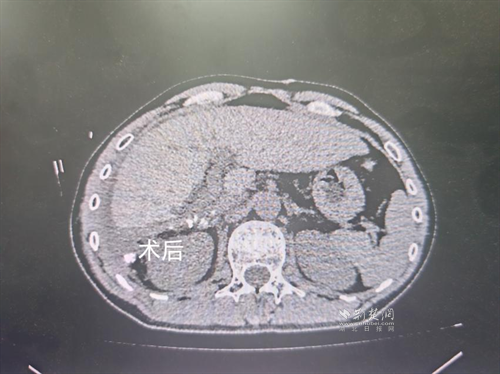

經(jīng)過肝膽外科牽頭組織的多學科MDT會診,團隊確認其適合接受當前國際先進的釔90樹脂微球選擇性內放射治療。治療僅一個月后,患者病灶即從10cm縮小至6cm;術后六個月復查顯示,病灶體積進一步縮小近40%,影像學檢查提示完全緩解,臨床分期成功轉化,達到手術切除標準。